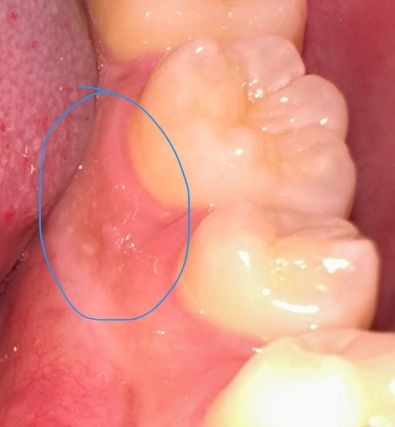

이렇게 작고 하얗고 혀로 만지면 까끌한 느낌은 주는게 몇주째있는데 혹시나 구강암처럼 심각한게 아닌지 궁금해요 어떤 걸까요?....

구내염 및 잇몸의 염증 등의 가능성이 있어 증상지속시 치과에 내원하시어 검진을 받아보시는 것을 추천드립니다.